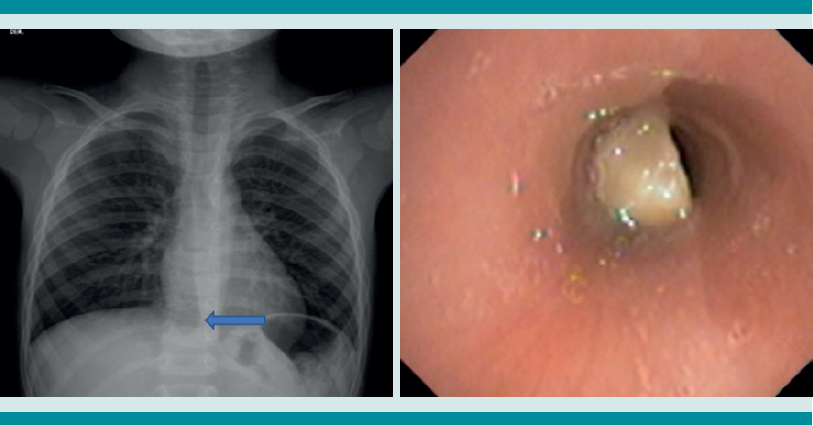

La radiografía de tórax es el primer estudio en un paciente pediátrico que llega al servicio de urgencias con sospecha de aspiración de cuerpo extraño. Gran parte de los objetos aspirados son radiolúcidos (biológicos y plásticos) y, por lo tanto, no se ven por este medio. Solo se logrará observar el cuerpo extraño en 15% de los casos (metálicos y huesos).1,6,8 Es más común identificar datos indirectos (aparecen hasta en 50% de las radiografías), que son consecuencia de la obstrucción en la vía aérea (atrapamiento de aire, atelectasias, consolidación, neumotórax) (Figuras 1,2,3,4,5). Respecto de las radiografías de tórax es que, incluso 45% pueden interpretarse normales, lo que puede resultar en un diagnóstico erróneo.1,6,9

Si al momento de consultar el paciente se encuentra en la etapa aguda, pero está estable, es decir, sin datos clínicos de inestabilidad cardiorrespiratoria, o se encuentra en la etapa oligosintomática pueden solicitarse los estudios de imagen. La radiografía de tórax es el principal recurso con el que cuentan la mayor parte de los servicios de urgencias. Es rápido, fácil, poco costoso y no requiere sedación. En caso de que sea un objeto radio-opaco, aportará el diagnóstico de manera rápida, y dará la localización del objeto (Figura 7). En caso de ser radiolúcido, la radiografía puede ser normal o mostrar los datos indirectos de obstrucción comentados. La tomografía axial computada de tórax puede considerarse si se cuenta con el recurso, tomando en cuenta lo mencionado.